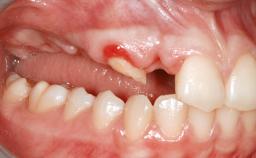

A 20-year-old woman was referred for implant therapy in 2004. Her medical history revealed no significant findings, and neither did she smoke nor take any medications. An extraoral examination revealed no abnormalities of the skin, hair or nails. The intraoral examination revealed only 11 permanent teeth clinically. These were normal in shape, size, and color. In addition, eight retained deciduous teeth (53, 62, 63, 71, 72, 73, 81, 82) were present. No abnormalities were detected during the general examination. The family history revealed that the patient’s father and two sisters were on record with similar conditions. The clinical examination revealed a thick gingival biotype. No recession of the attached gingiva was noted, but the retained deciduous teeth were mobile and unsightly. As a syndrome had not been diagnosed, the case was categorized as non-syndromic oligodontia.

Soft Tissue Anatomy Intact Defective

Bone Volume Horizontally and vertically sufficient Horizontally deficient Deficient vertically or deficient vertically AND horizontally

Bone Volume Deficient horizontally, requiring prior grafting